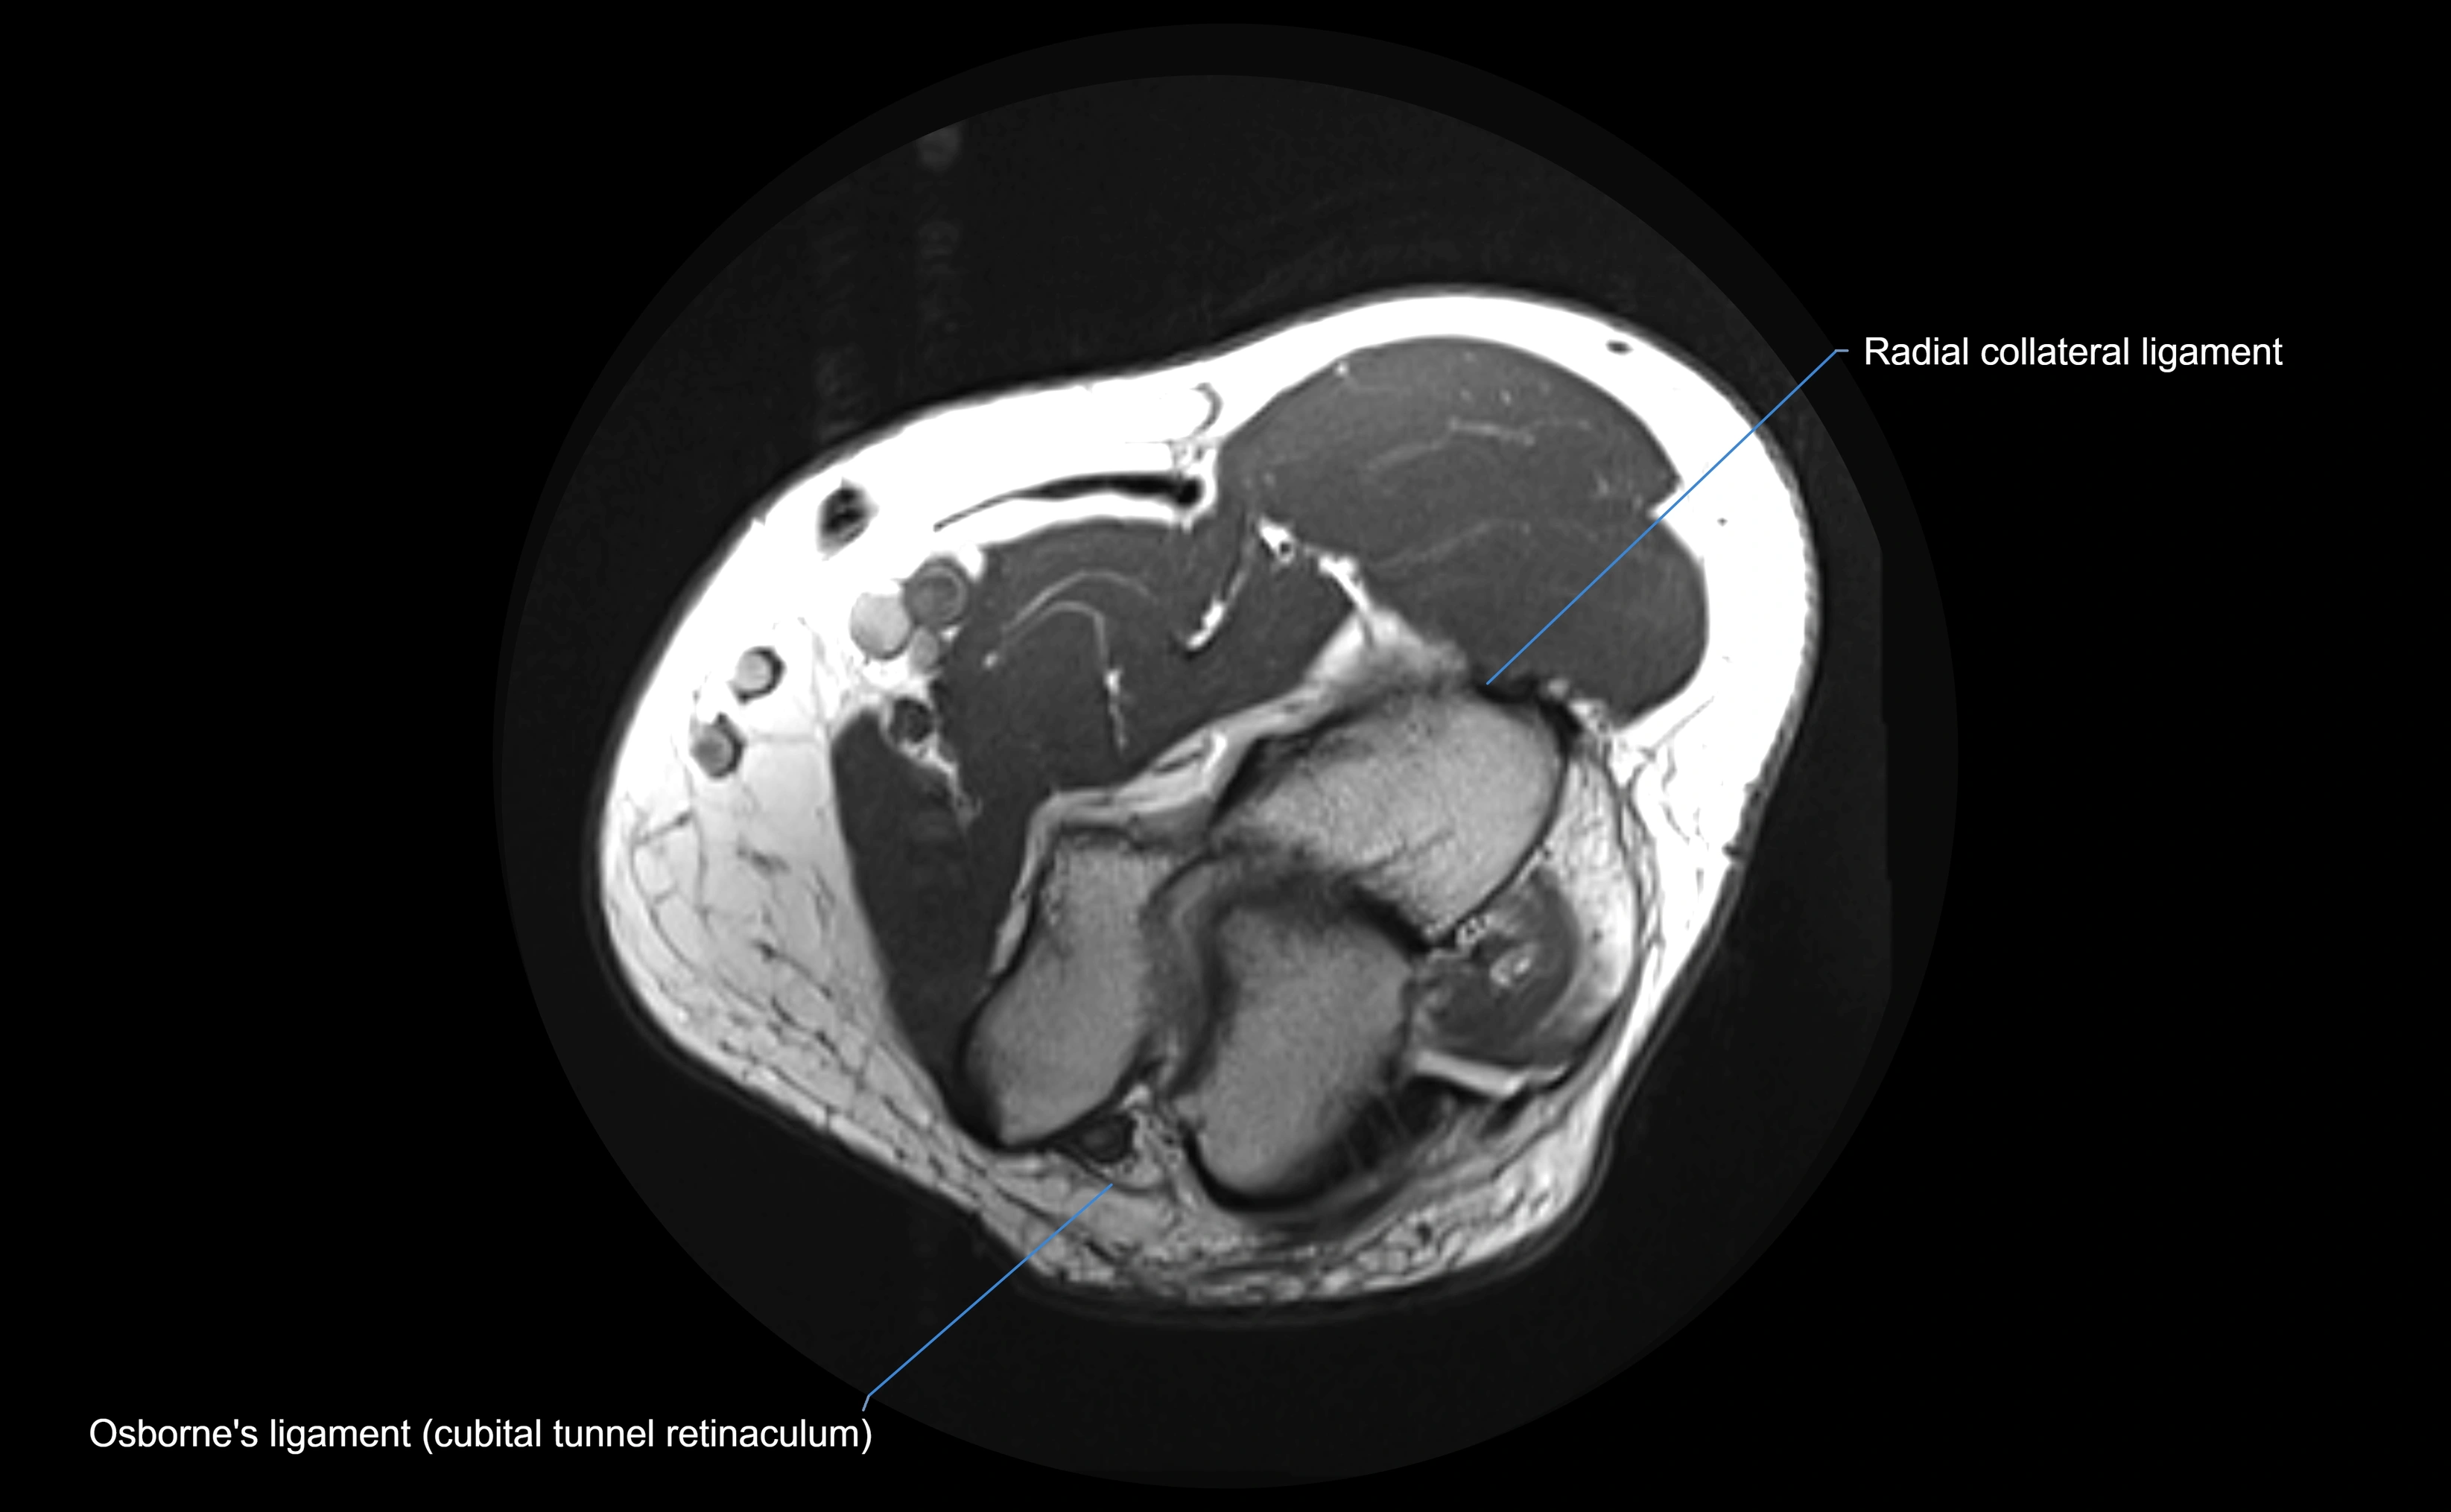

MRI Appearance

T1-weighted images:

• Ligament: low signal intensity (dark), appearing as a continuous band around the radial head.

• Adjacent fat and marrow: bright, creating contrast with the ligament.

• Thickening or disruption indicates injury or fibrosis.

• Joint capsule and synovium seen as thin low-signal lines contiguous with ligament margins.

T2-weighted images:

• Ligament: low signal (dark) with clear delineation from joint fluid.

• Fluid or edema: bright hyperintense, separating or surrounding the ligament in partial tears.

• Complete tear: discontinuity or non-visualization of ligament fibers, often with joint effusion.

Proton Density Fat-Saturated (PD FS):

• Normal: dark, well-defined band outlining the radial head.

• Partial tear: irregular or bright hyperintense signal within or adjacent to ligament fibers.

• Joint effusion and reactive synovitis appear bright and are well visualized.